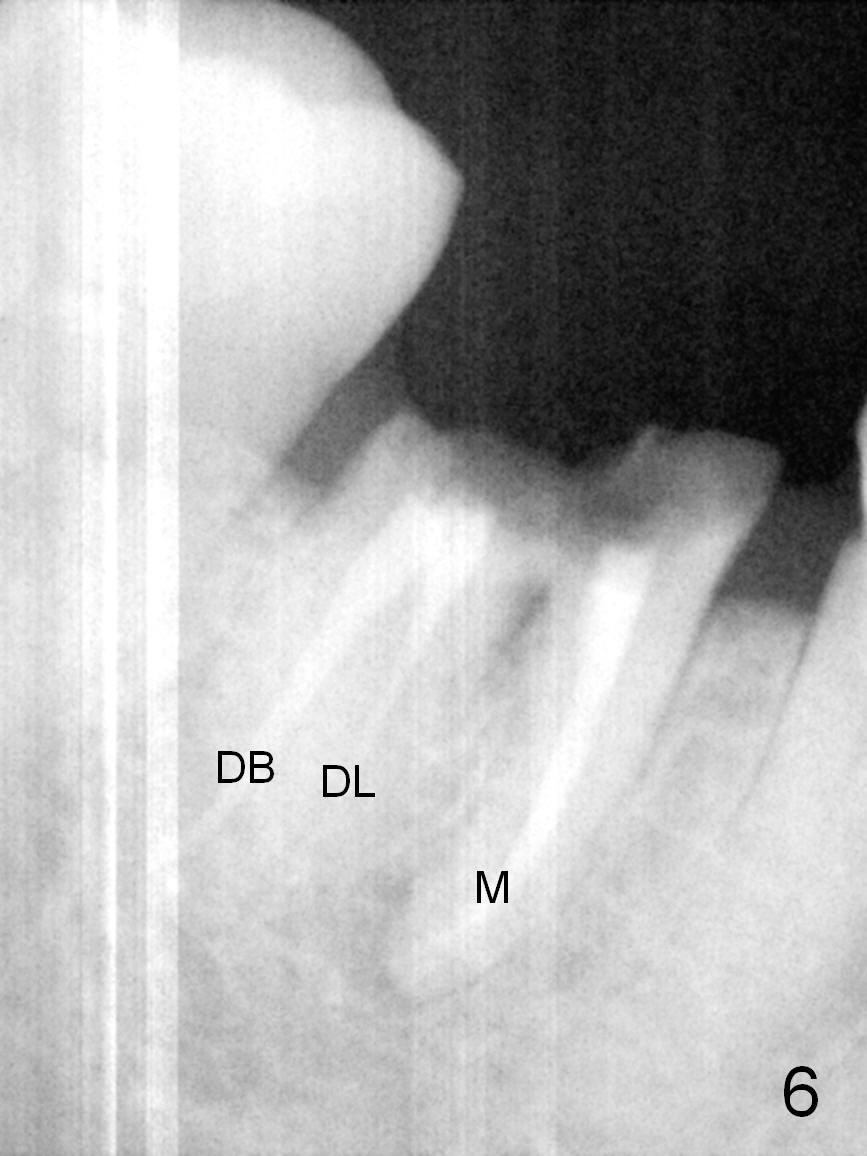

A 68-year-old lady (WQ) had CT taken 3 years ago (Fig.1-3), which show 3 roots (M: mesial; DB: distobuccal; DL: distolingual) of the lower right 1st molar and large caries (C).  Recently the tooth fractures after root canal therapy (Fig.4-6).

Having 3 roots suggests a tripod septum.  Surgical handpiece and elevators may be required, in addition to proximators.  Cowhorn forceps should be helpful.  The socket will be treated with Clindamycin, selected by time sequence.